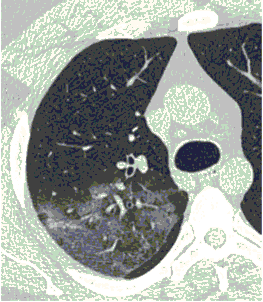

КТ имеет высокую чувствительность в выявлении изменений в легких, характерных для COVID-19. Применение КТ целесообразно для первичной оценки состояния ОГК у пациентов с тяжелыми прогрессирующими формами заболевания, а также для дифференциальной диагностики выявленных изменений и оценки динамики процесса. КТ позволяет выявить характерные изменения в легких у пациентов с COVID-19 еще до появления положительных лабораторных тестов на инфекцию с помощью МАНК. В то же время, КТ выявляет изменения легких у значительного числа пациентов с бессимптомной и легкой формами заболевания, которым не требуется госпитализация. Результаты КТ в этих случаях не влияют на тактику лечения и прогноз заболевания при наличии лабораторного подтверждения COVID-19. Поэтому массовое применение КТ для скрининга асимптомных и легких форм болезни не рекомендуется. При первичном обращении пациента с подозрением на COVID-19 рекомендуется назначать КТ только при наличии клинических и инструментальных признаков дыхательной недостаточности (SpO2 < 95%, ЧДД > 22).

3. Применение лучевых методов у пациентов с симптомами ОРВИ легкой степени тяжести и стабильном состоянии пациента, возможно только по конкретным клиническим показаниям, в том числе при наличии факторов риска, при условии достаточных технических и организационных возможностей. Методом выбора в этом случае является КТ легких по стандартному протоколу без внутривенного контрастирования или РГ при ограниченной доступности КТ. Использование УЗИ в этих случаях нецелесообразно. Применение КТ исследования в сроки ранее 3 - 5 дней с момента появления симптомов заболевания, а также при отсутствии клинических проявлений поражения бронхолегочной системы является нецелесообразным. Выполнение КТ целесообразно при наличии клинических и инструментальных признаков дыхательной недостаточности (SpO2 < 95%, ЧДД > 22), либо при дифференциальной диагностике с другим заболеванием.

- оптимально: выполнение КТ исследования легких по стандартному протоколу без внутривенного контрастирования;